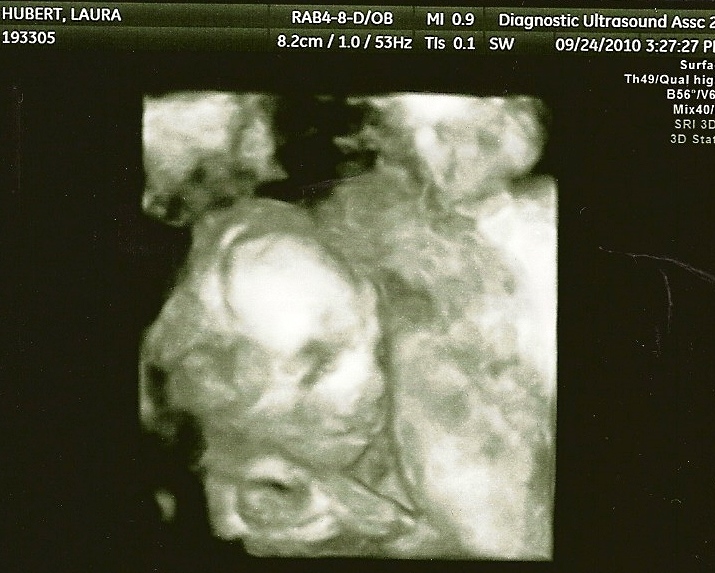

Ultrasound Pictures

18 weeks

9/24/10